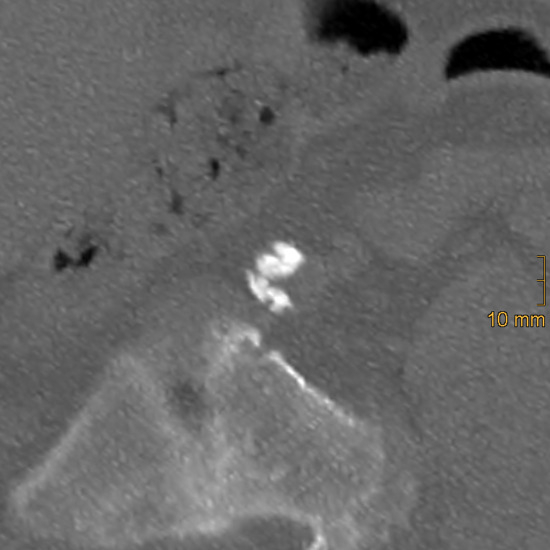

Concurrent Congenital Umbilicobiliary Fistula and Vesicourachal Diverticula in a Dog

Congenital umbilicobiliary fistula is a rare disease reported in humans and dogs. A 2-month-old, intact, male French Bulldog presented with a greenish-yellow discharge dripping from the umbilicus since birth. Complete blood count and serum biochemistry were within normal limits, but serum alkaline phosphatase [...] Read more.

Congenital umbilicobiliary fistula is a rare disease reported in humans and dogs. A 2-month-old, intact, male French Bulldog presented with a greenish-yellow discharge dripping from the umbilicus since birth. Complete blood count and serum biochemistry were within normal limits, but serum alkaline phosphatase activity was mildly elevated. A positive contrast cystogram was performed to rule out a patent urachus and confirmed the presence of a vesicourachal diverticula, a type of urachal anomalies. An abdominal ultrasound and computed tomography fistulogram demonstrated a communication between the umbilicus and common bile duct, which suggested an umbilicobiliary fistula. Surgical correction of the umbilicobiliary fistula and vesicourachal diverticula was successfully performed with an uneventful recovery. Histological analysis of the fistulous tract demonstrated a cuboidal/columnar lining epithelium that transitioned to squamous epithelium near the umbilicus. Agenesis of the gallbladder was noted. The application of multiple imaging techniques in the diagnosis and surgical correction of these congenital abnormalities (umbilicobiliary fistula, gallbladder agenesis, and vesicourachal diverticula) was beneficial for treatment planning and outcome. Full article